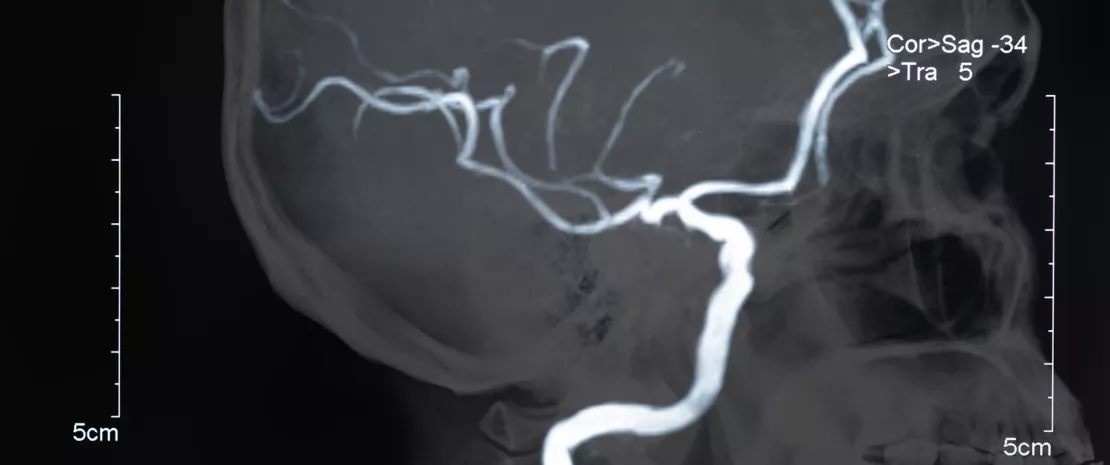

Photo : Gut dysbiosis index to assess the prognosis of stroke

Avec près de 25 millions d’épisodes annuels, l’AVC ischémique aigu représente un enjeu de santé publique majeur à l’échelle mondiale. Le pronostic est pour l’heure complexe à établir et pourrait bénéficier de l’identification de facteurs de risque d’évolution péjorative. Ce constat a poussé une équipe chinoise à mettre au point le Stroke Dysbiosis Index (SDI), un indice reliant AVC et dysbiose intestinale. Son objectif : confirmer l’accident et déterminer la sévérité des lésions cérébrales ainsi que le risque de complications précoces.

La seconde partie de l’étude a été réalisée chez la souris, afin de préciser in vivo la relation entre dysbiose intestinale et répercussions d’un AVC ischémique aigu. Des occlusions de l’artère cérébrale moyenne ont été provoquées chez des animaux ayant reçu des transplantations fécales de patients humains présentant un SDI faible ou élevé. Résultat : des lésions cérébrales aggravées et des taux élevés de lymphocytes T -δ producteurs d’IL-17 (cytokine pro-inflammatoire) observés chez les animaux colonisés par les bactéries signatures d’un SDI élevé comparativement aux souris recevant des transplants de patients ayant un SDI bas. La preuve d’un effet négatif d’une dysbiose intestinale sur le pronostic post-AVC. Le microbiote et sa modulation, notamment par des pré- ou des probiotiques, représentent donc pour l’équipe une approche thérapeutique à explorer, en vue de maximiser les chances de récupération des patients AVC.